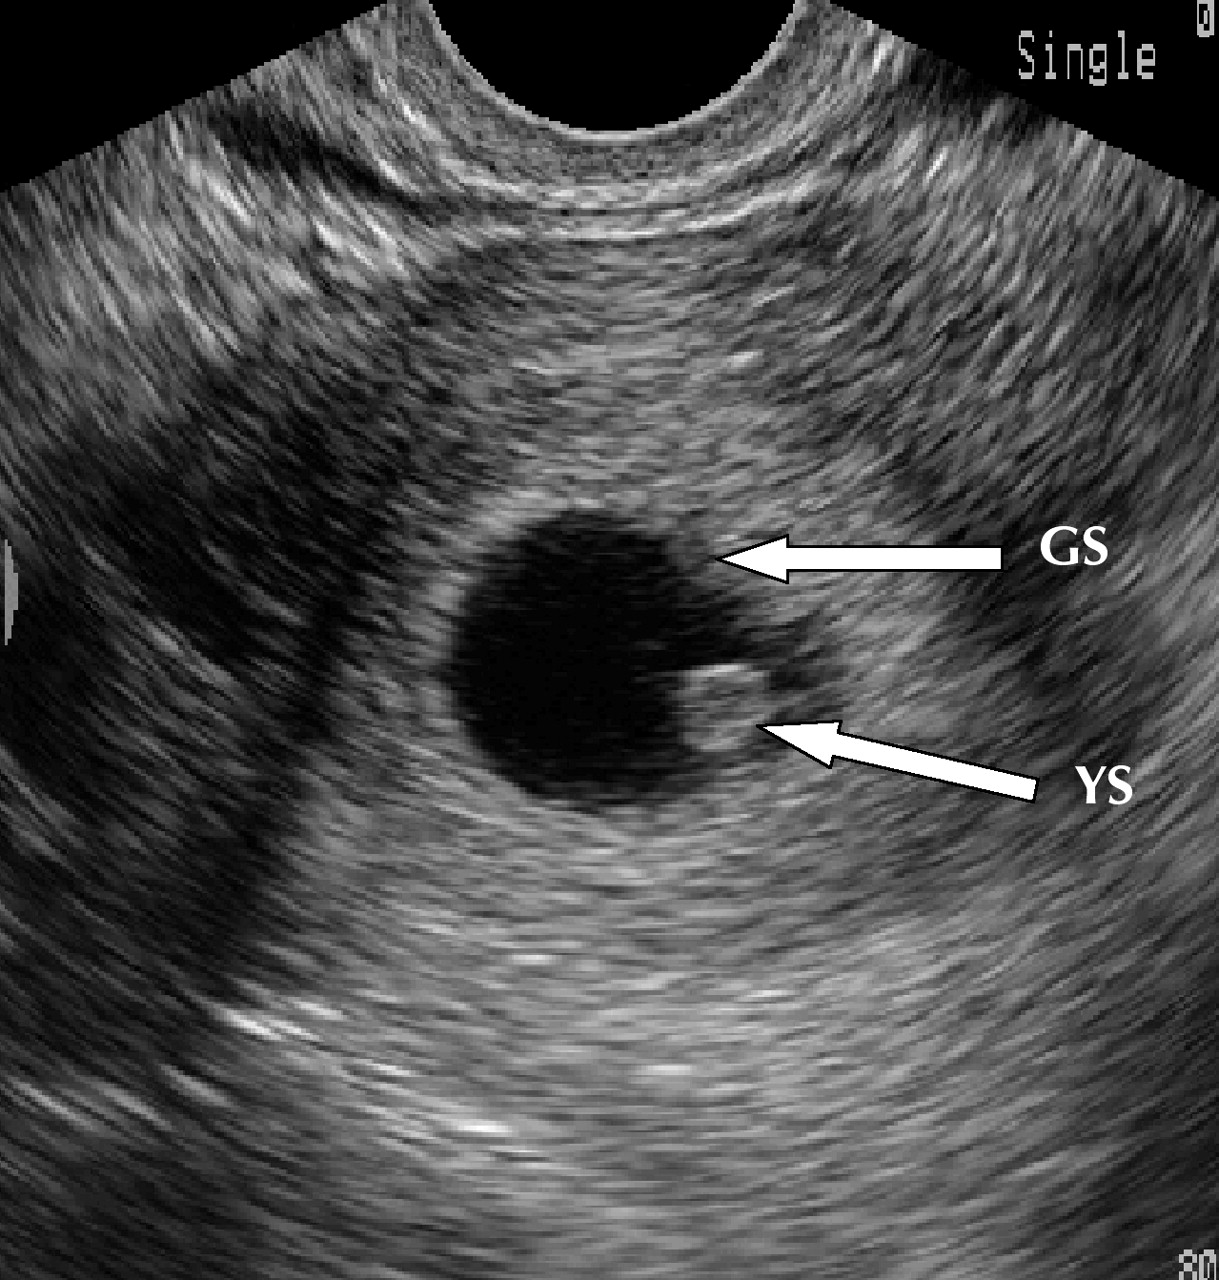

Ultrasound Leadership Academy: Ultrasound in Early Pregnancy — EM Curious

PV Card: Focused 1st Trimester Pregnancy Transvaginal Ultrasound